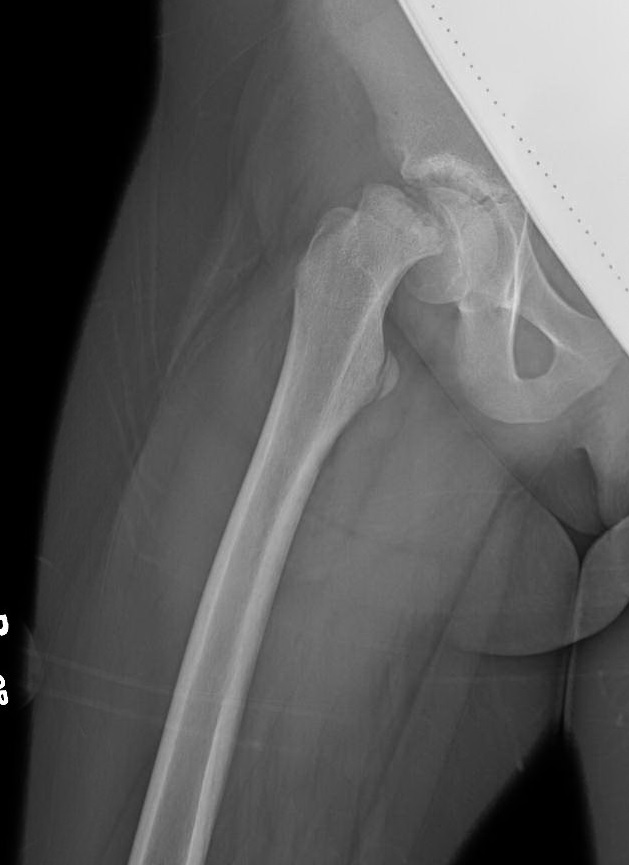

Slipped Capital Femoral Epiphysis Gepost op 28 juli 201728 juli 2017 door netwerkvsseh Back to Basics: Slipped Capital Femoral Epiphysis @emdaily.cooperhealth.com Dit delen: Delen op X (Opent in een nieuw venster) X Share op Facebook (Opent in een nieuw venster) Facebook Delen op LinkedIn (Opent in een nieuw venster) LinkedIn E-mail een link naar een vriend (Opent in een nieuw venster) E-mail Afdrukken (Opent in een nieuw venster) Print Vind-ik-leuk Aan het laden... Gerelateerd